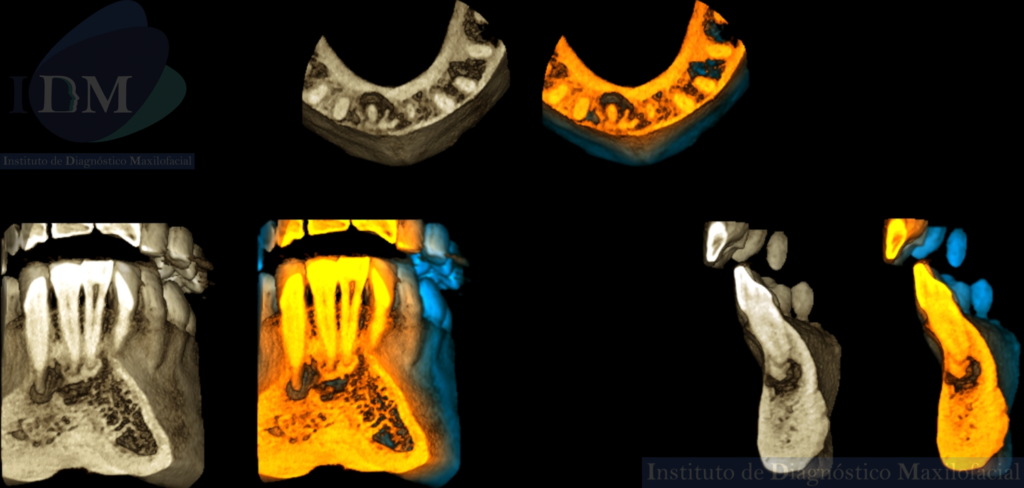

A la evaluación de la radiografía panorámica se evidencian múltiples imágenes mixtas y de forma irregular en zona apical de las piezas 41, 42 y 43.

Así mismo en la tomografía volumétrica de haz cónico de campo reducido evidenciamos que dichas imágenes mixtas se encuentran comprometiendo zona a pical de la pieza 41 y 42 con un aumento de la densidad ósea adyacente. Siendo la imagen hipodensa a nivel a pical de la pieza 43 una probable lesión apical.

RECONSTRUCCIÓN 3D